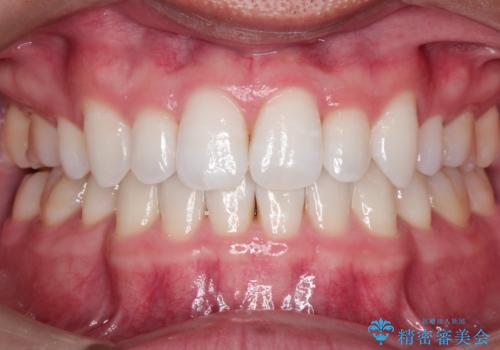

- 患者様は、歯並びのガタガタ(重度の叢生)を改善したいとのことで来院されました。診察すると、歯列のスペース不足が著しく、前歯が重なり合い、噛み合わせにも影響が出ている状態でした。歯をきれいに並べるためには抜歯によるスペース確保が不可欠と判断し、上下の小臼歯4本を抜歯したうえで、目立ちにくい審美ワイヤー矯正(白いワイヤーと透明ブラケット)を用いた治療計画を立てました。

抜歯によって歯を動かすためのスペースを確保。その後、審美ワイヤー矯正を用いて歯を1本ずつ適切な位置に誘導しながら、噛み合わせのバランスも整えていきました。時間はかかりましたが、ガタガタの歯並びがきれいに整い、機能的にも審美的にも満足のいく仕上がりとなりました。患者様からは「歯並びが劇的に改善し、見た目だけでなく噛みやすさも向上した」と喜びの声をいただきました。